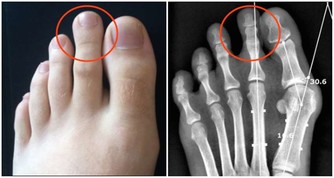

6、 遺傳因素也是一方面,痛風是一種遺傳代謝性疾病,具有遺傳性。患有痛風病的家族裡,如果不調節自己的飲食習慣,就很容易患上痛風。因為體內缺少一種酶,就不能把蛋白質分解。最後結晶成小晶體堆積在關節內,誘發疾病。

根據調查顯示:痛風患者的初發平均年齡在不到20年的時間裡下降了6.3歲,開始襲擊年輕人。據分析發現,痛風的初次發病年齡有明顯年輕化的趨勢,不足40歲的初次發病者增加了26.3%。

年輕人患痛風的原因是什麼呢?專家認為,攝入富含嘌呤類食物(含有嘌呤代謝紊亂的食物如動物內臟,魚蝦蛋白以及啤酒等,肝,腎,肉餡,肉汁,肉湯,鯖魚,風尾魚,沙丁魚,魚卵,小蝦,淡菜,鵝,斑雞,石雞等含嘌呤都很高,再者熏火腿,豬肉,牛肉,兔肉,鴨,鴿,貝殼類含嘌呤也是比較高的,如果有痛風就不建議吃這些食物。)者迅速增多是主要原因。人們的飲食結構已經發生了明顯的變化,尤其是20歲至40歲的年輕人飲食中含高能量、高嘌呤類物質者顯著增加。數據顯示:20歲至40歲年齡組的痛風病人發病前,90%以上有經常大量飲酒和嗜好吃肉、動物內臟、海鮮等富含嘌呤類成分食物的習慣。

調查發現,在40歲以下的痛風患者中,約85%的人體重超重。由於工作繁忙等原因,在40歲以下的痛風人群中,多數人起居不規律,體力活動越來越少,出門坐車者增多,騎自行車、步行者漸少。生活富裕,又缺少足夠的體育鍛煉,肥胖是必然的趨勢。研究結果證明,血尿酸水平與體重指數呈正相關。